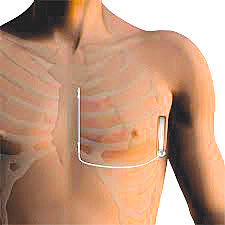

Σε ασθενή με καρδιακή ανεπάρκεια που κινδύνευε από αιφνίδιο θάνατο εμφυτεύθηκε υποδόριος απινιδωτής αφήνοντας ανέγγιχτα την καρδιά και τα αγγεία.

Ο υποδόριος απινιδωτής αποτελεί εξέλιξη των τελευταίων ετών και έχει σκοπό να αφήσει τα αγγεία και την καρδιά εντελώς ανέγγιχτα αφού τοποθετείται εξ ολοκλήρου κάτω από το δέρμα, μειώνοντας στο ελάχιστο, τις πιθανές επιπλοκές της αγγειακής προσπέλασης και της ενδοκαρδιακής τοποθέτησης των ηλεκτροδίων των συμβατικών απινιδωτών.Να σημειωθεί οτι στο Εργαστήριο πραγματοποιούνται σήμερα όλες οι τεχνικές της σύγχρονης Επεμβατικής Αρρυθμιολογίας από την ομάδα η οποία απαρτίζεται από τον καθηγ. κ. Ε. Σημαντηράκη και τους ιατρούς Ε.Σ.Υ κ. Ε. Καλλέργη και κ. Η. Μαυράκη.